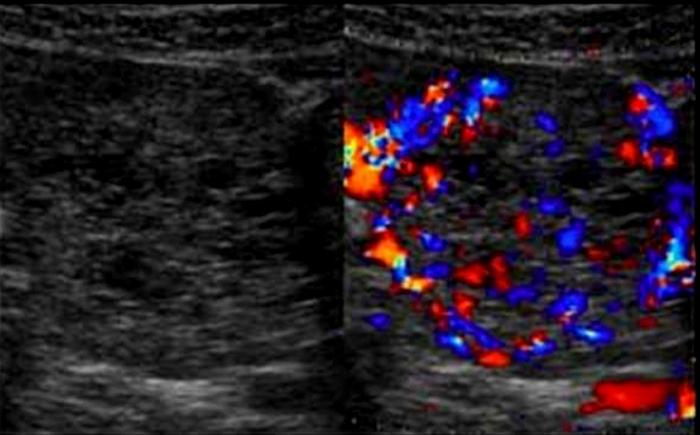

Varicocele

left side

most common correctible cause of male infertility

Varicocele